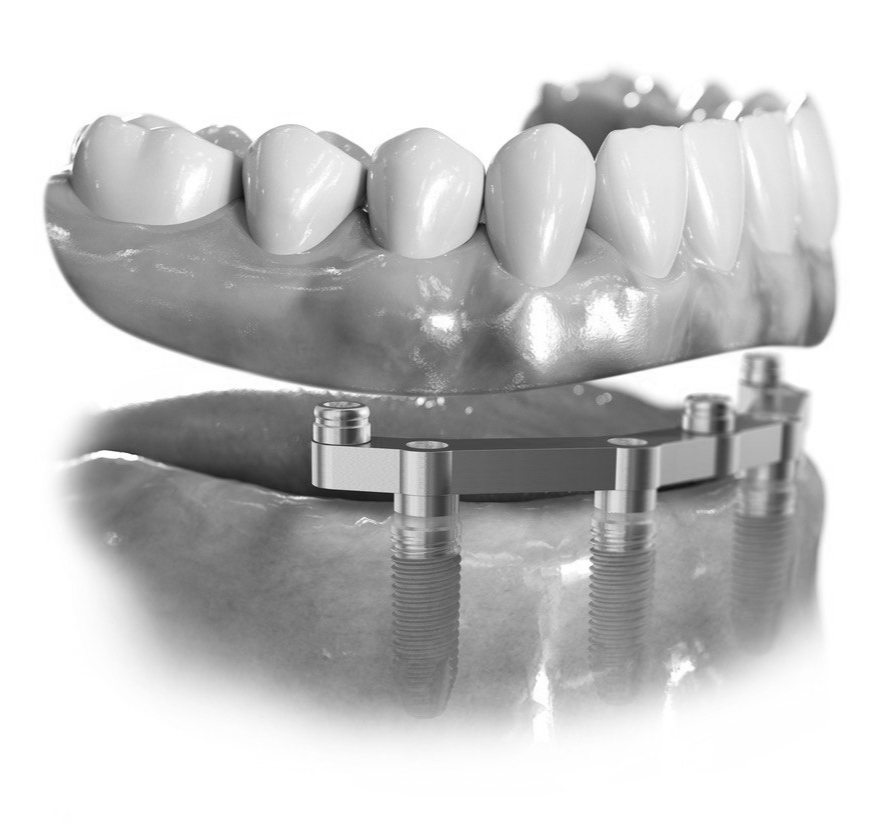

Изготовление постоянного, а не временного протеза "Все на 4" или "Все на 6" сразу после имплантации. Благодаря отточенной и слаженной работе, мы изготавливаем сразу постоянный несъемный протез с металлической балкой и опорой на имплантах, в то время как многие наши коллеги изготавливают временный или адаптационный протез, который необходимо будет заменить на постоянный через 6 месяцев. С нашим протезом нужно будет сделать только перебазировку через полгода, это занимает всего один день, и пользоваться им можно долгие годы.

Цена «под ключ» с постоянным несъемным протезом «Все на 4»

«Все на 4». По швейцарской технологии на имплантах OSSTEM (Ю. Корея)